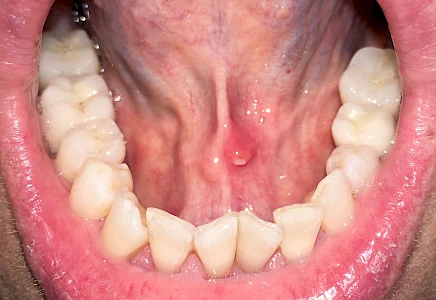

Mandelstein

Mandelsteine (Tonsillenstein oder auch Tonsillolith) sind Reste von Gewebe, Speisen, Entzündungszellen und Bakterien können vereinzelt im Bereich der Gaumenmandeln beobachtet werden. Ggf. sollten die aktuellen Mundpflegemaßnahmen überprüft und ggf. angepasst werden.